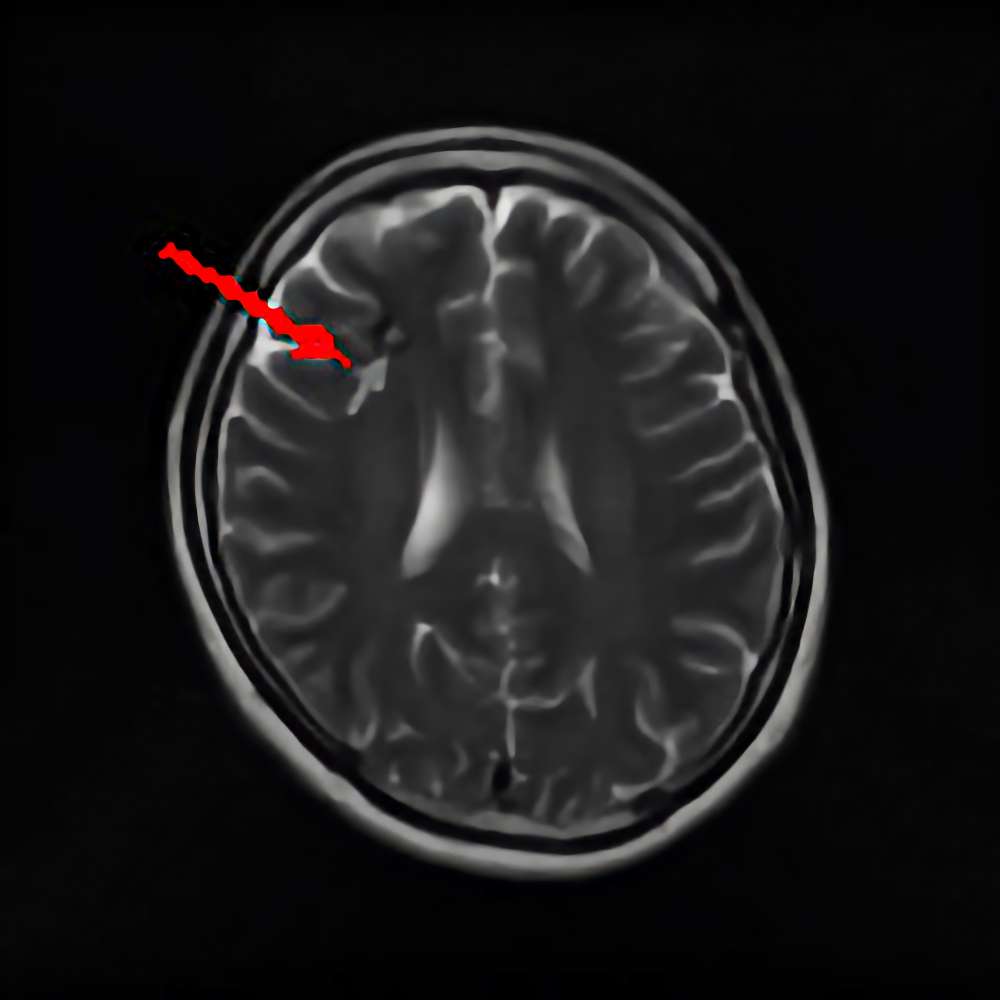

断層撮影

手術前1

手術前2